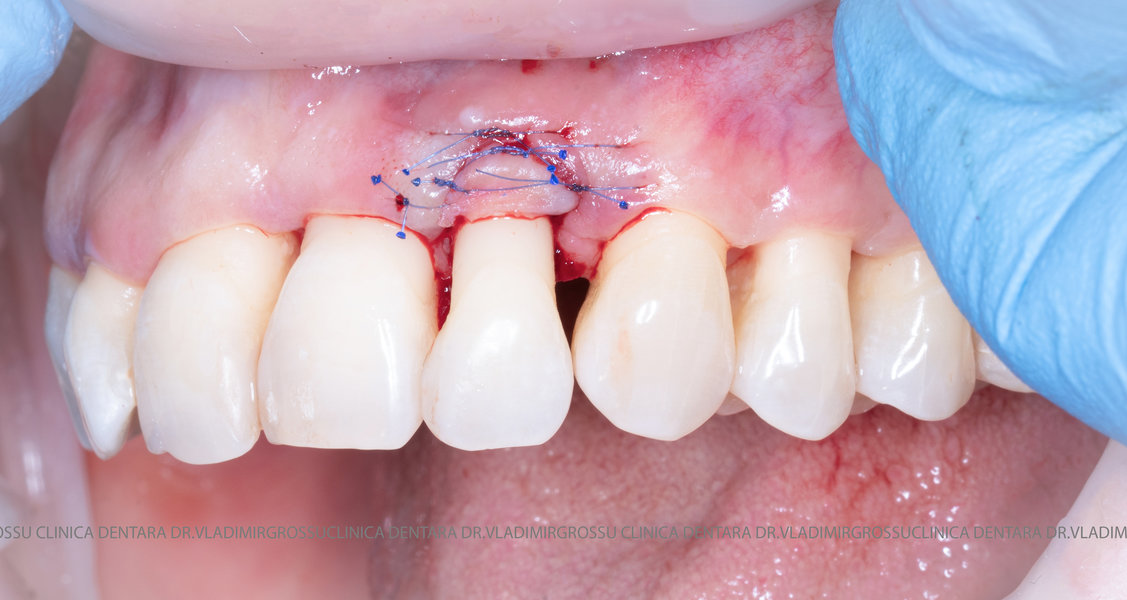

Aditia gingivală este o procedură chirurgicală ce corectează diverse probleme estetice și funcționale, cum ar fi recesiunea gingivală. În implantologia modernă, aditia de țesut moale este utilizată aproape în fiecare intervenție de inserție a implantului dentar pentru a asigura un aspect estetic natural și o bună integrare a implantului în cavitatea bucală.

Adiția osoasă are un rol crucial pentru poziționarea corectă și stabilă a implanturilor dentare. Clinica stomatologică Dr. Grossu din Chișinău promovează o abordare chirurgicală estetică și predictibilă, adaptată fiecărui caz în parte.

Medicii noștri au o vastă experiență atât în chirurgia estetică, cât și în protezarea cu un grad înalt de naturalitate, ceea ce ne permite să gestionăm cu succes și cele mai complexe cazuri.